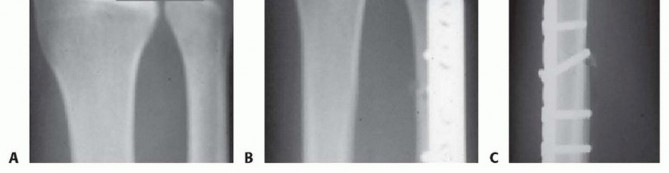

Make an 8- to 10-cm incision over the subcutaneous border of the ulna as previously described (TECH FIG 1A).Elevate the ECU muscle-tendon from the distal dorsal aspect of the ulna to allow sufficient room for a six-or seven-hole AO dynamic compression plate (Synthes LC-DCP, Synthes, Paoli, PA) (TECH FIG 1B).Take care to avoid disrupting the ECU subsheath distally.

TECH FIG 1 • A. An 8- to 10-cm incision over the subcutaneous border of the ulna. B. Six-hole AO-type dynamic compression plate (DCP) (Synthes). Avoid interfering with the osteotomy when placing the pins by referring to the line drawn at the proposed osteotomy site.Place the pins palmar enough to allow the plate to be securely seated over the dorsal surface of the ulna.

TECH FIG 5 • A. Posteroanterior (PA) wrist radiograph showing ulnar positive variance. B,C. PA and lateral radiographs after ulnar shortening osteotomy. The interfragmentary lag screw compresses the osteotomy site.